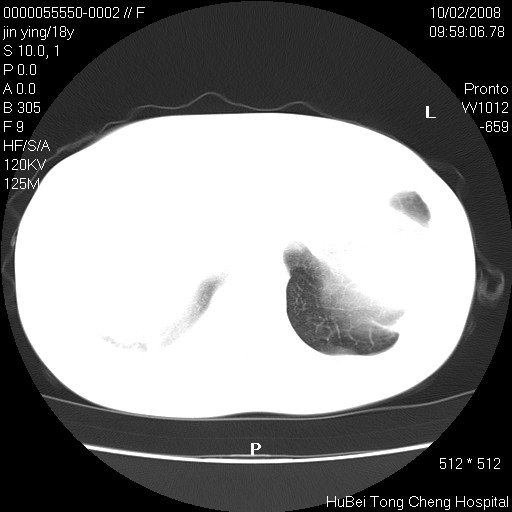

患者 女,18y。发热十余天,伴咳嗽。pe:t39⒈℃,bp 110/80mmhg,p 86次/min。神清,精神欠佳。双肺可闻及少许湿罗音。既往史不详。

临床诊断:肺部感染?

胸部ct轴位平扫(层厚10mm,螺距1.5,重建间隔10mm),图像如下: